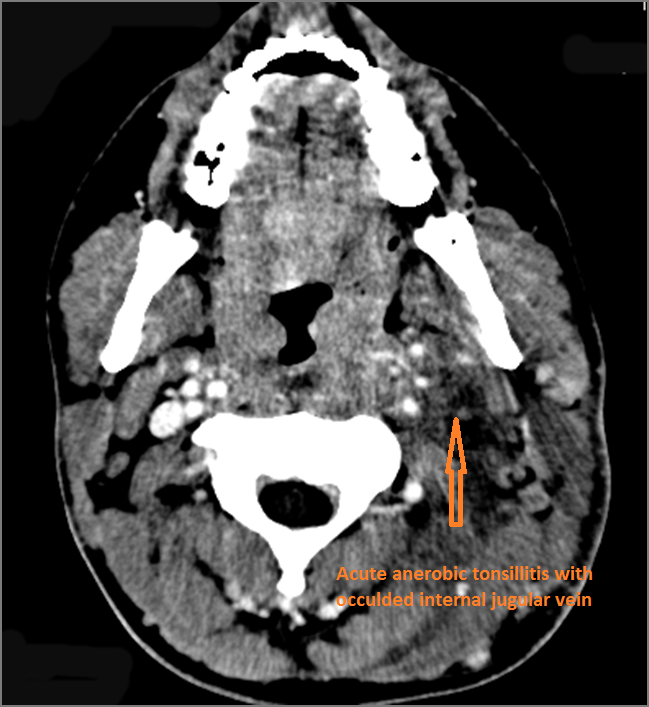

Vascular Findings

If there is suppurative cervical adenopathy the purulent material outside the lymph node(s) capsule(s).